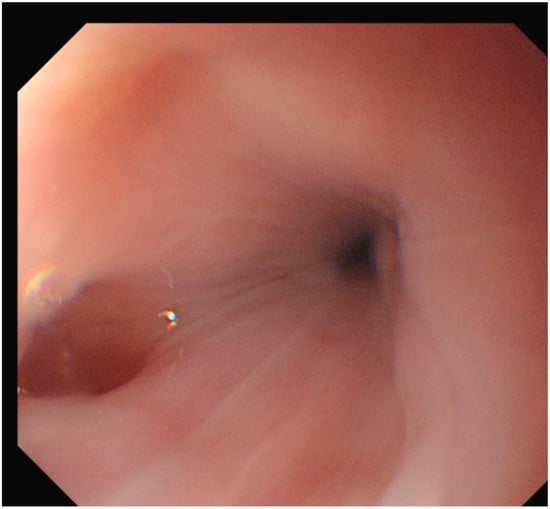

In addition to standardized lateral cephalometric radiographs, comprehensive assessment using dental cone-beam computed tomography (CBCT) and CT has become commonplace in the diagnosis and treatment of jaw deformities. Simulation based on cephalometr...